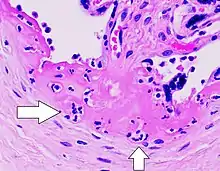

- Villitis, inflamación de las vellosidades coriónicas.

- Intervillositis, inflamación del espacio intervelloso.[1]

La VUE es una lesión común caracterizada por inflamación en las vellosidades coriónicas placentarias. También se caracteriza por la transferencia de linfocitos maternos a través de la placenta.[4]